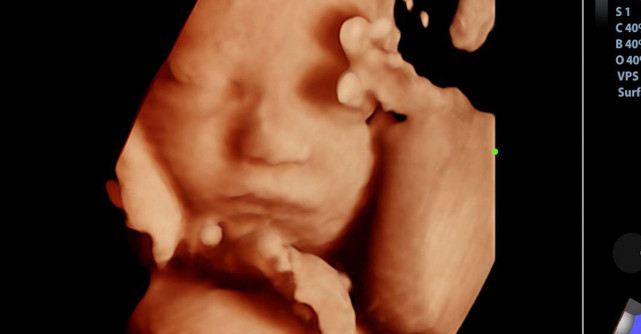

Dacă în ecografiile 2D imaginea obținută se aseamănă unei secțiuni, în cazul ecografiilor 3D/4D imaginile sunt interpretate spațial, astfel încât se poate investiga corpul bebelușului în dezvoltare, chipul, sexul, membrele, se pot face măsurători etc.

• Săptămânile 24-34 de sarcină: considerată de către specialiști ca fiind cel mai potrivit moment pentru ecografiile 3D/4D, deoarece bebelușul este dezvoltat suficient de mult pentru a putea fi observat în detaliu, pentru a i se poza chipul și expresia fetei, bebelușul având totodată suficient spațiu pentru a se mișca în mediul uterin, fiind astfel ușor de surprins din mai multe unghiuri.